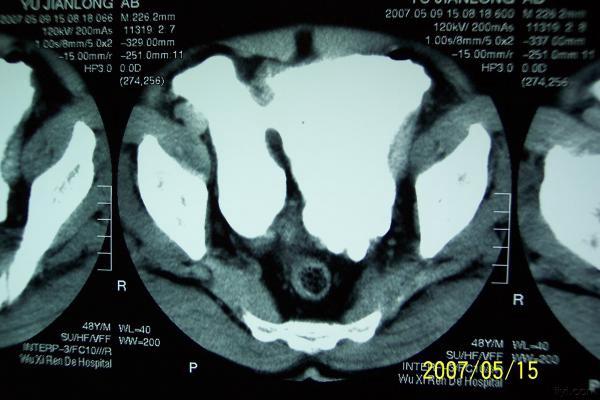

分享下一例巨大膀胱憩室的图片

分享下一例罕见病历的图片,这是我遇到的最大巨大膀胱憩室。

双膀胱,少见,要看输尿管注入膀胱的位置。

考虑双膀胱的可能性大.

双膀胱畸形